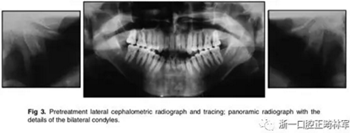

X片示:垂直向生長過度,下頜后縮、上頜前突,上切牙前傾、前突,下切牙前突但唇舌向傾角正常;雙側(cè)髁突畸形,提示退行性變。

影像學(xué):全景片示:牙根平行度可。頭顱側(cè)位片及疊加圖示:下頜骨發(fā)生逆時(shí)針旋轉(zhuǎn),面部輪廓改善;上切牙轉(zhuǎn)矩正常,下切牙輕微舌傾;唇突度減小,鼻唇角增大。